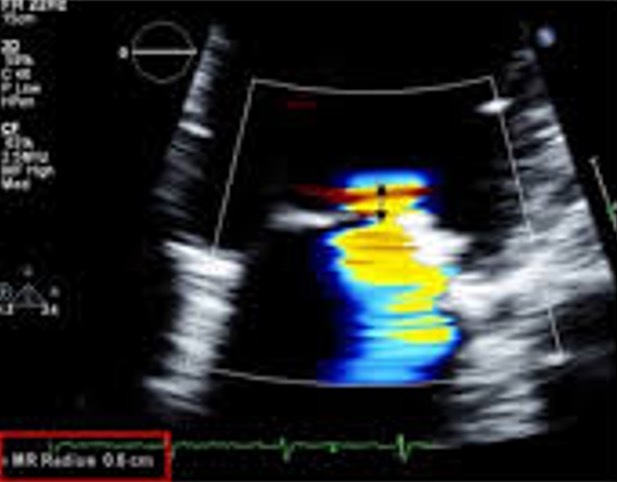

The LVOT and AV colour doppler here is what?

Aliased in the normal heart

Color aliasing can be a helpful artifact in echo to do what?

Accessing valve pathology

What is valvular regurgitation?

Valvular regurgitation occurs when a valve cannot coapt, or close correctly resulting in leakage, or backward flow through the valve

What timeframe does valvular regurgitation occur?

During the timeframe the valve should normally be closed